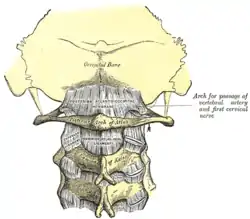

Second cervical vertebra, or epistropheus, from above | |

Its shape and position (shown in red) from above. The skull is shown in semi-transparent. Axis seen from above

Axis seen from above 3D image

3D image Posterior atlantooccipital membrane and atlantoaxial ligament; the axis is visible at center.

Posterior atlantooccipital membrane and atlantoaxial ligament; the axis is visible at center. Median sagittal section through the occipital bone and first three cervical vertebra